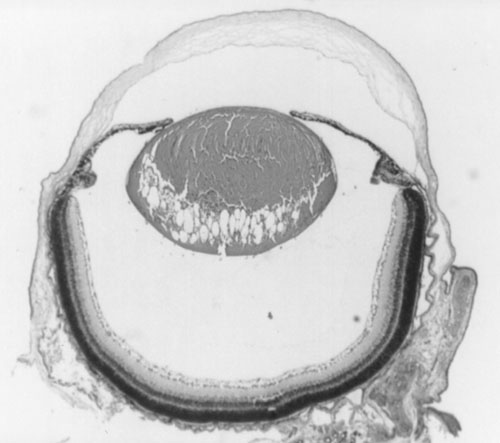

Figure 2. Histology of Ccw/+ eyes

A. Normal littermate 10 days post partum. B. Ccw/+ 10 days post partum. Some vacuolation of the lens is visible. C. Ccw/+ 20 days post partum. Lens fibers are becoming swollen and disorganized. D. Ccw/+ 4-6 weeks post partum. Lens fibers are largely degraded. E. Ccw/+ 14 weeks post partum. Only the lens capsule and some epithelium remain.

B.